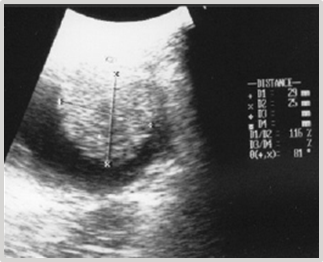

This case involves a 9-year-old female mixed-breed canine, referred for intermittent mild hematuric cystitis. Clinical examination of the abdominal cavity through palpation reveals the presence of a painless, immobile mass with a semi-soft and fixed consistency within the bladder. The ultrasonographic diagnosis reveals the presence of a heterogeneous element with irregular borders and a hypoechoic center, attached to the ventral wall and near the vesical neck, measuring 1.90 cm x 1.85 cm (Figure 1).

Figure 1 Ultrasonographic diagnosis of bladder: Heterogeneous element with irregular borders measuring 1.90 cm x 1.85 cm.